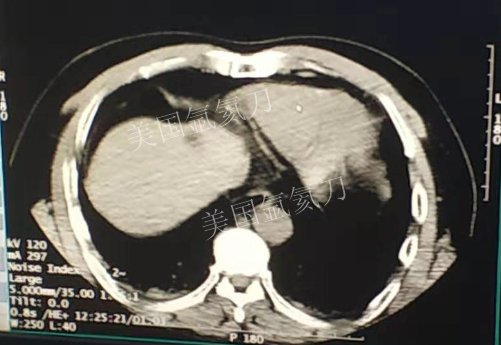

59岁男性肝部氩氦刀手术治疗